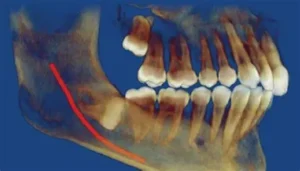

Wisdom teeth, also known as third molars, are the last set of teeth at the back of your mouth. These teeth typically emerge in late